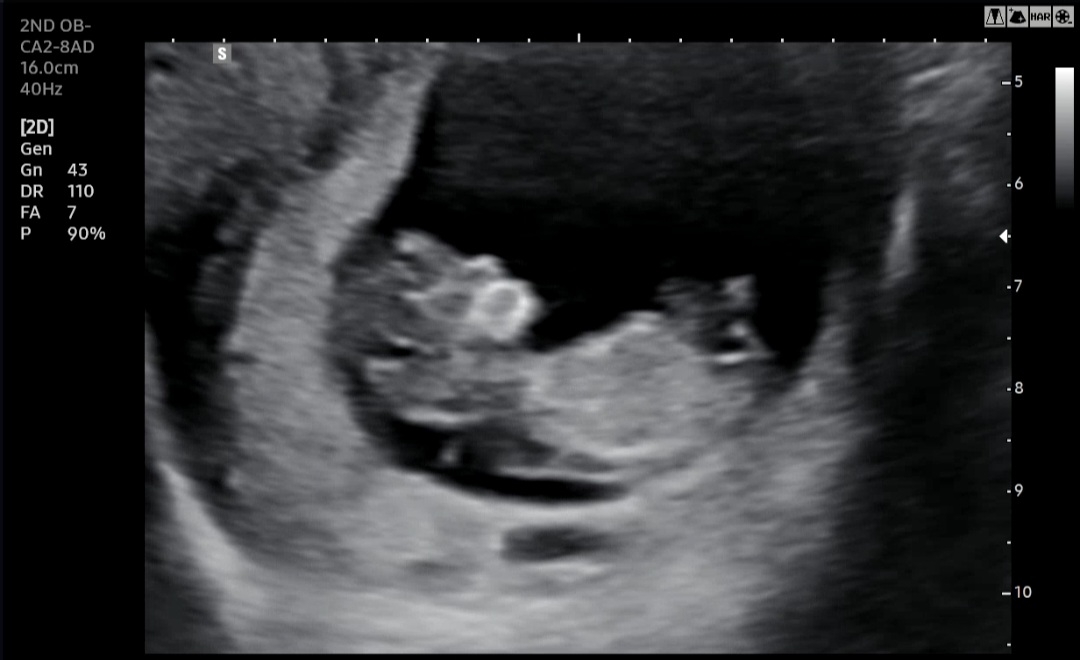

주수상 10주5일인데 촘파상 보니 11주1일ㅜ 태명 처럼 무럭무럭 잘 자라구있구나 콧대도보이고 목선도보이구ㅜ 몇일사이 머리부터 엉덩이까지 4.37cm까지 자라고 ㅜㅜ 뭉클...

와우 정말 콧대가 잘 보이네요!! 곧 12주!! 수고하셨어요 ~~